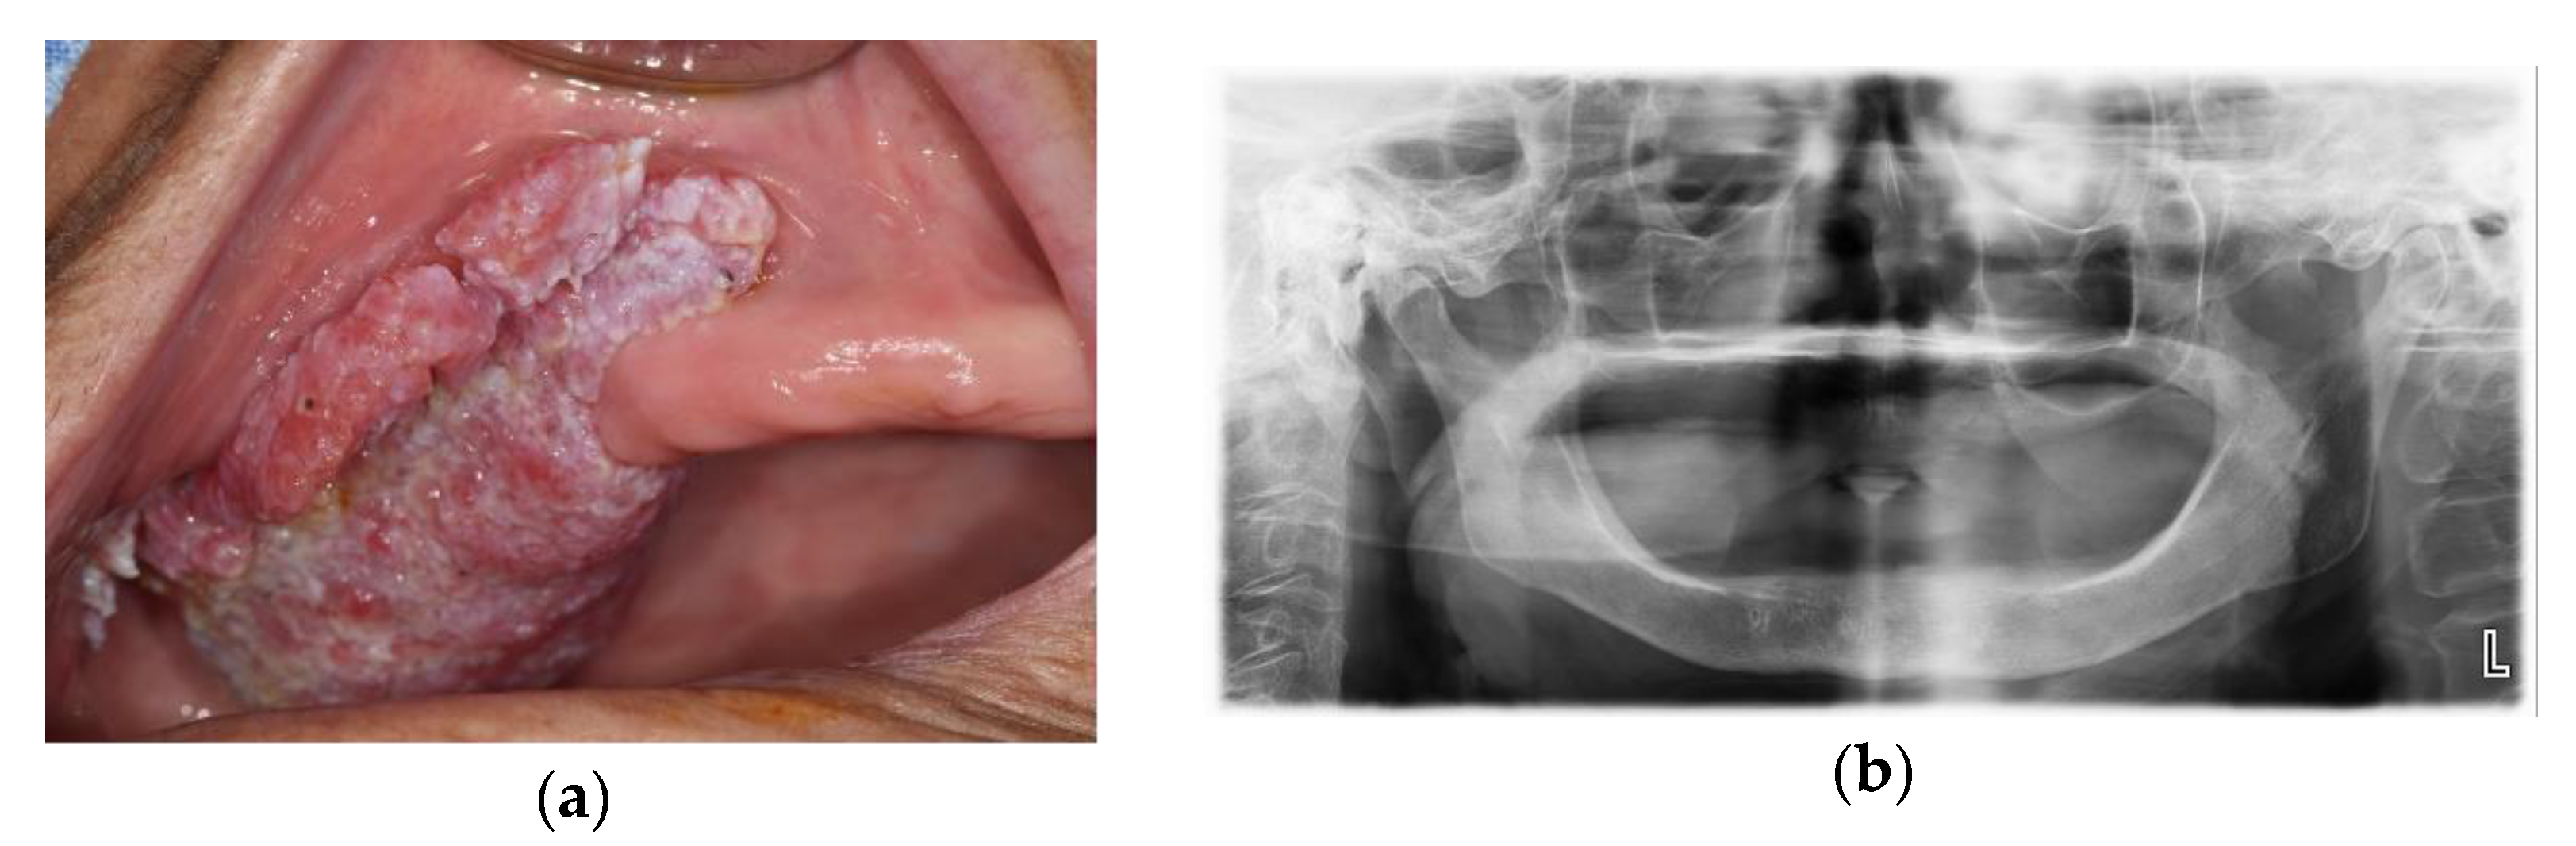

A 78-year-old female presented at the department of oral and maxillofacial surgery with a growing mass on the right upper gingiva (Figure 10).

Figure 10.

Initial examinations: (a) intraoral photograph showed the proliferative lesion with indistinct borders on the right upper gingiva; (b) panoramic view.

An incisional biopsy diagnosed a verrucous carcinoma. CT and PET-CT were taken. A palatal lesion with intense fluorodeoxyglucose (FDG) uptake was observed on the radiological images. Therefore, a partial maxillectomy and DCIA flap reconstruction were planned.